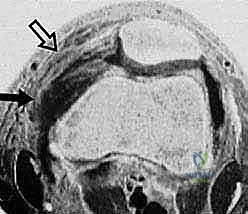

Historically, the orthopedic community oscillated between conservative management and non-anatomic medial reefing procedures for acute dislocations. However, the paradigm has shifted dramatically toward anatomic, pathology-specific interventions. By identifying the exact location of the MPFL tear via high-resolution magnetic resonance imaging (MRI), surgeons can now tailor their approach. A discrete avulsion off the proximal two-thirds of the medial patella, with robust, unretracted ligamentous tissue, presents the ideal scenario for primary repair. This masterclass will delineate the precise steps required to execute this repair, ensuring anatomic restoration, preventing over-constraint, and optimizing long-term functional outcomes.

Advanced cross-sectional imaging, specifically MRI and occasionally CT, is indispensable. Axial CT or MRI is used to accurately measure the TT-TG offset, ensuring it falls within the acceptable range (< 15-20 mm) for an isolated MPFL procedure.

However, MRI is the primary modality for evaluating the soft-tissue envelope. We scrutinize the T2-weighted axial and coronal sequences to identify the exact location of the MPFL failure. We look for the classic "wavy" appearance of a detached ligament, surrounding edema, and the presence of a distinct stump at the patellar margin.

Crucially, the MRI must be reviewed for concomitant articular cartilage damage; osteochondral loose bodies originating from the medial patellar facet or the lateral femoral condyle are common and must be addressed concurrently.